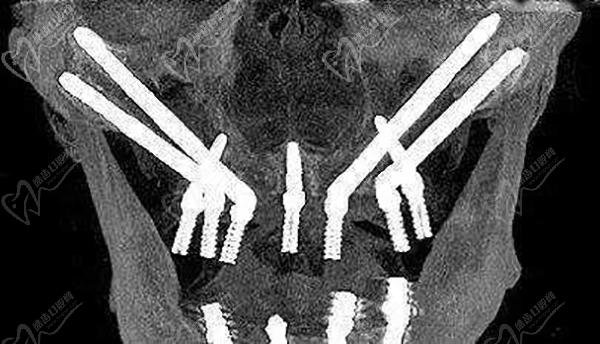

VIIV穿顴穿翼技術(shù)

相比傳統(tǒng)種植或all-on-4種植,其VIIV種植植體長(zhǎng)度更長(zhǎng),增加了種植穩(wěn)定性,同時(shí)有效縮短了種植治療周期。